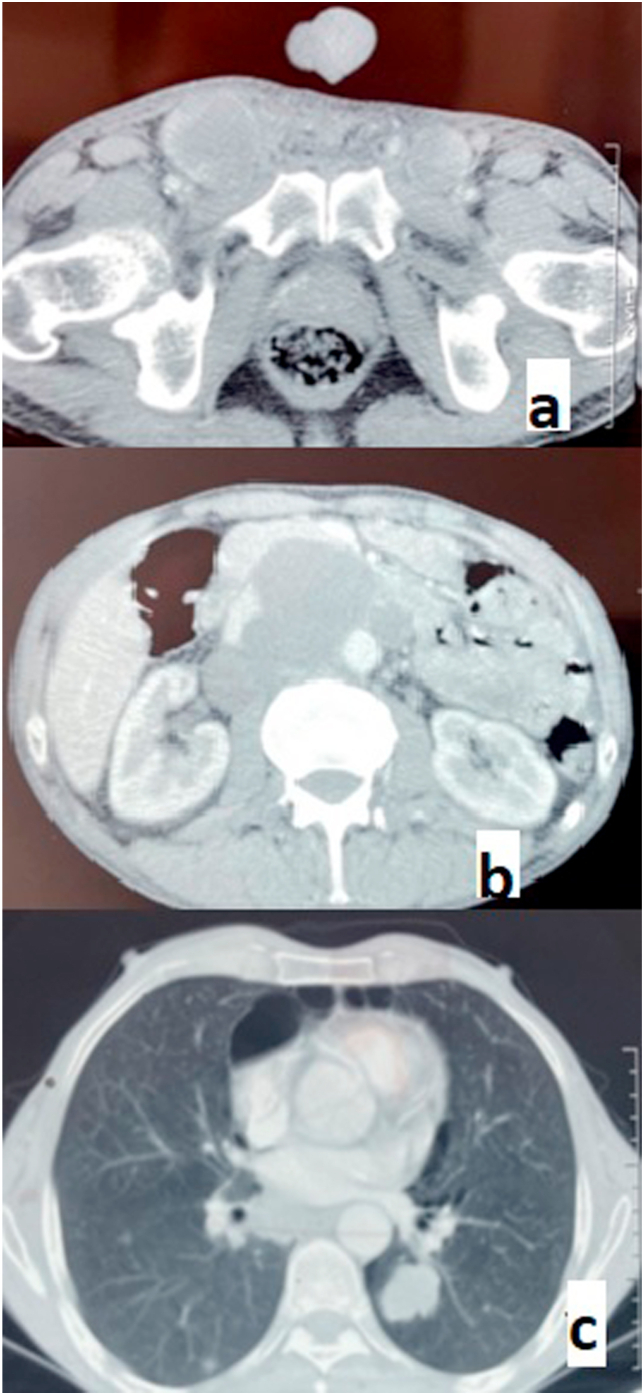

Tumour markers were significantly elevated, with alpha-fetoprotein (AFP) reaching 23,640 ng/ml and lactate dehydrogenase (LDH) at 807 IU/l. However, total human chorionic gonadotropin hormone (HCG) levels were normal. A thoracic-abdominal-pelvic CT scan confirmed the presence of para-aortic lymph nodes and lung metastases.(Fig. 3).

Fig. 3.

Images of CT sections showing: inguinal (a) and inter-aortic-caval (b) lymph node metastases and lung metastases (b).